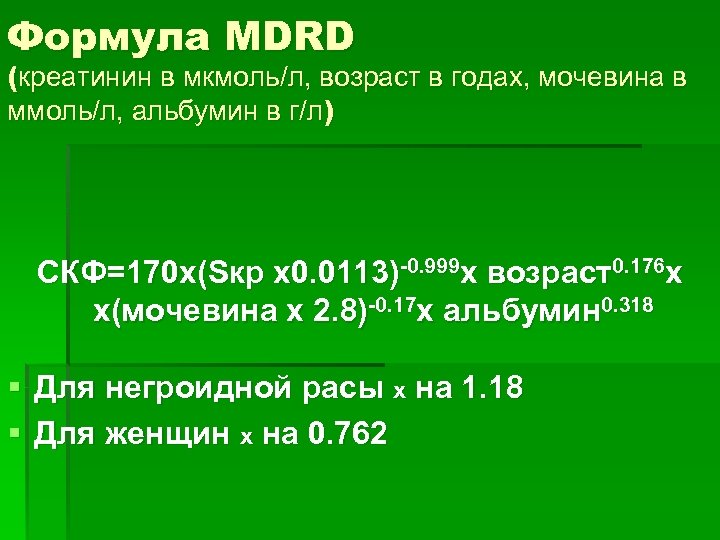

Формула MDRD (креатинин в мкмоль/л, возраст в годах, мочевина в ммоль/л, альбумин в г/л) СКФ=170 х(Sкр х0. 0113)-0. 999 х возраст0. 176 х х(мочевина х 2. 8)-0. 17 х альбумин 0. 318 § Для негроидной расы х на 1. 18 § Для женщин х на 0. 762